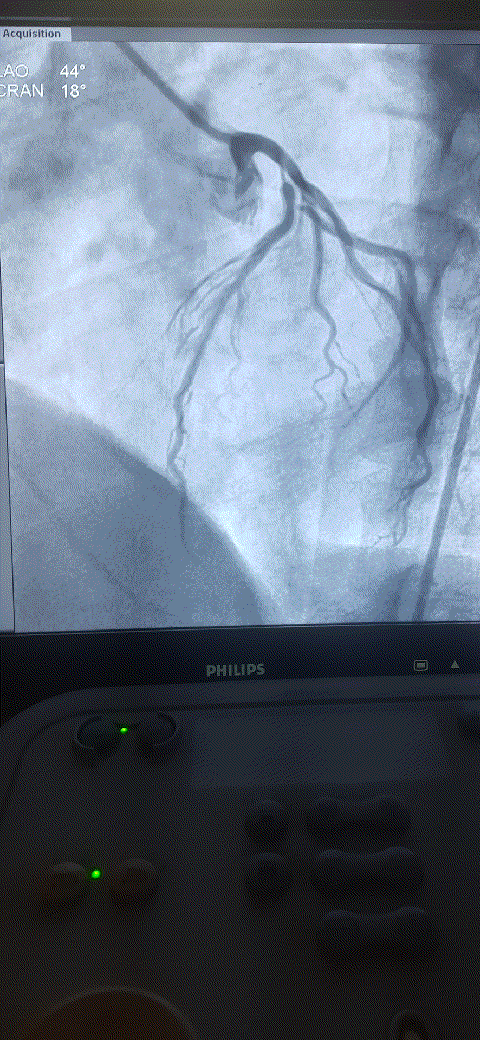

How do you explain this ? 99% occlusion still TIMI 3 flow ?

A. It could be a parallax error. Lesion may not be tight. Should be seen in other views.

B . Forcible Injection by the operator, make it an artificial TIMI -3 flow.

C .Such flows are very much possible .It Indicates a healthy distal micro-circulation a vascular bed in a fully dilated mode.

D. TIMI flow is not reliable here . We need TIMI frame count to confirm.

Follow up questions

1.How much will be the FFR ?

Likely to be less than . 8 definitely , but surprises can happpen

2.Can he be asymptomatic ?

Unlikely.

Final message

Coronary occlusions are ominpresent . While we have mastered the art of successfully taming these anatomical enemies , we are still very much ignorant what these lesions actually do, to the physiology, inspite of half a dozen flow reserve Indices we have.(FFR,iFR, rFR,qFR, dP/dT ,etc)

The question is, at what level of obstruction, it really limits the coronary bllod flow significantly ( both at rest and exertion) . One thing is clear , it is higly variable & Individualistic, the secrets of which lies deep, in the domain of invisible micro-vascular network integrity.

Counterpoint

TIMI flows may no longer be valid in non-ACS situations. The name TIMI , by itself carries flow after thrombolysis. For some unexplained (& debatable ) reasons, we are used to apply this flow grade , in every angiographic flow scenerios irrespective of underlying clinical entity.